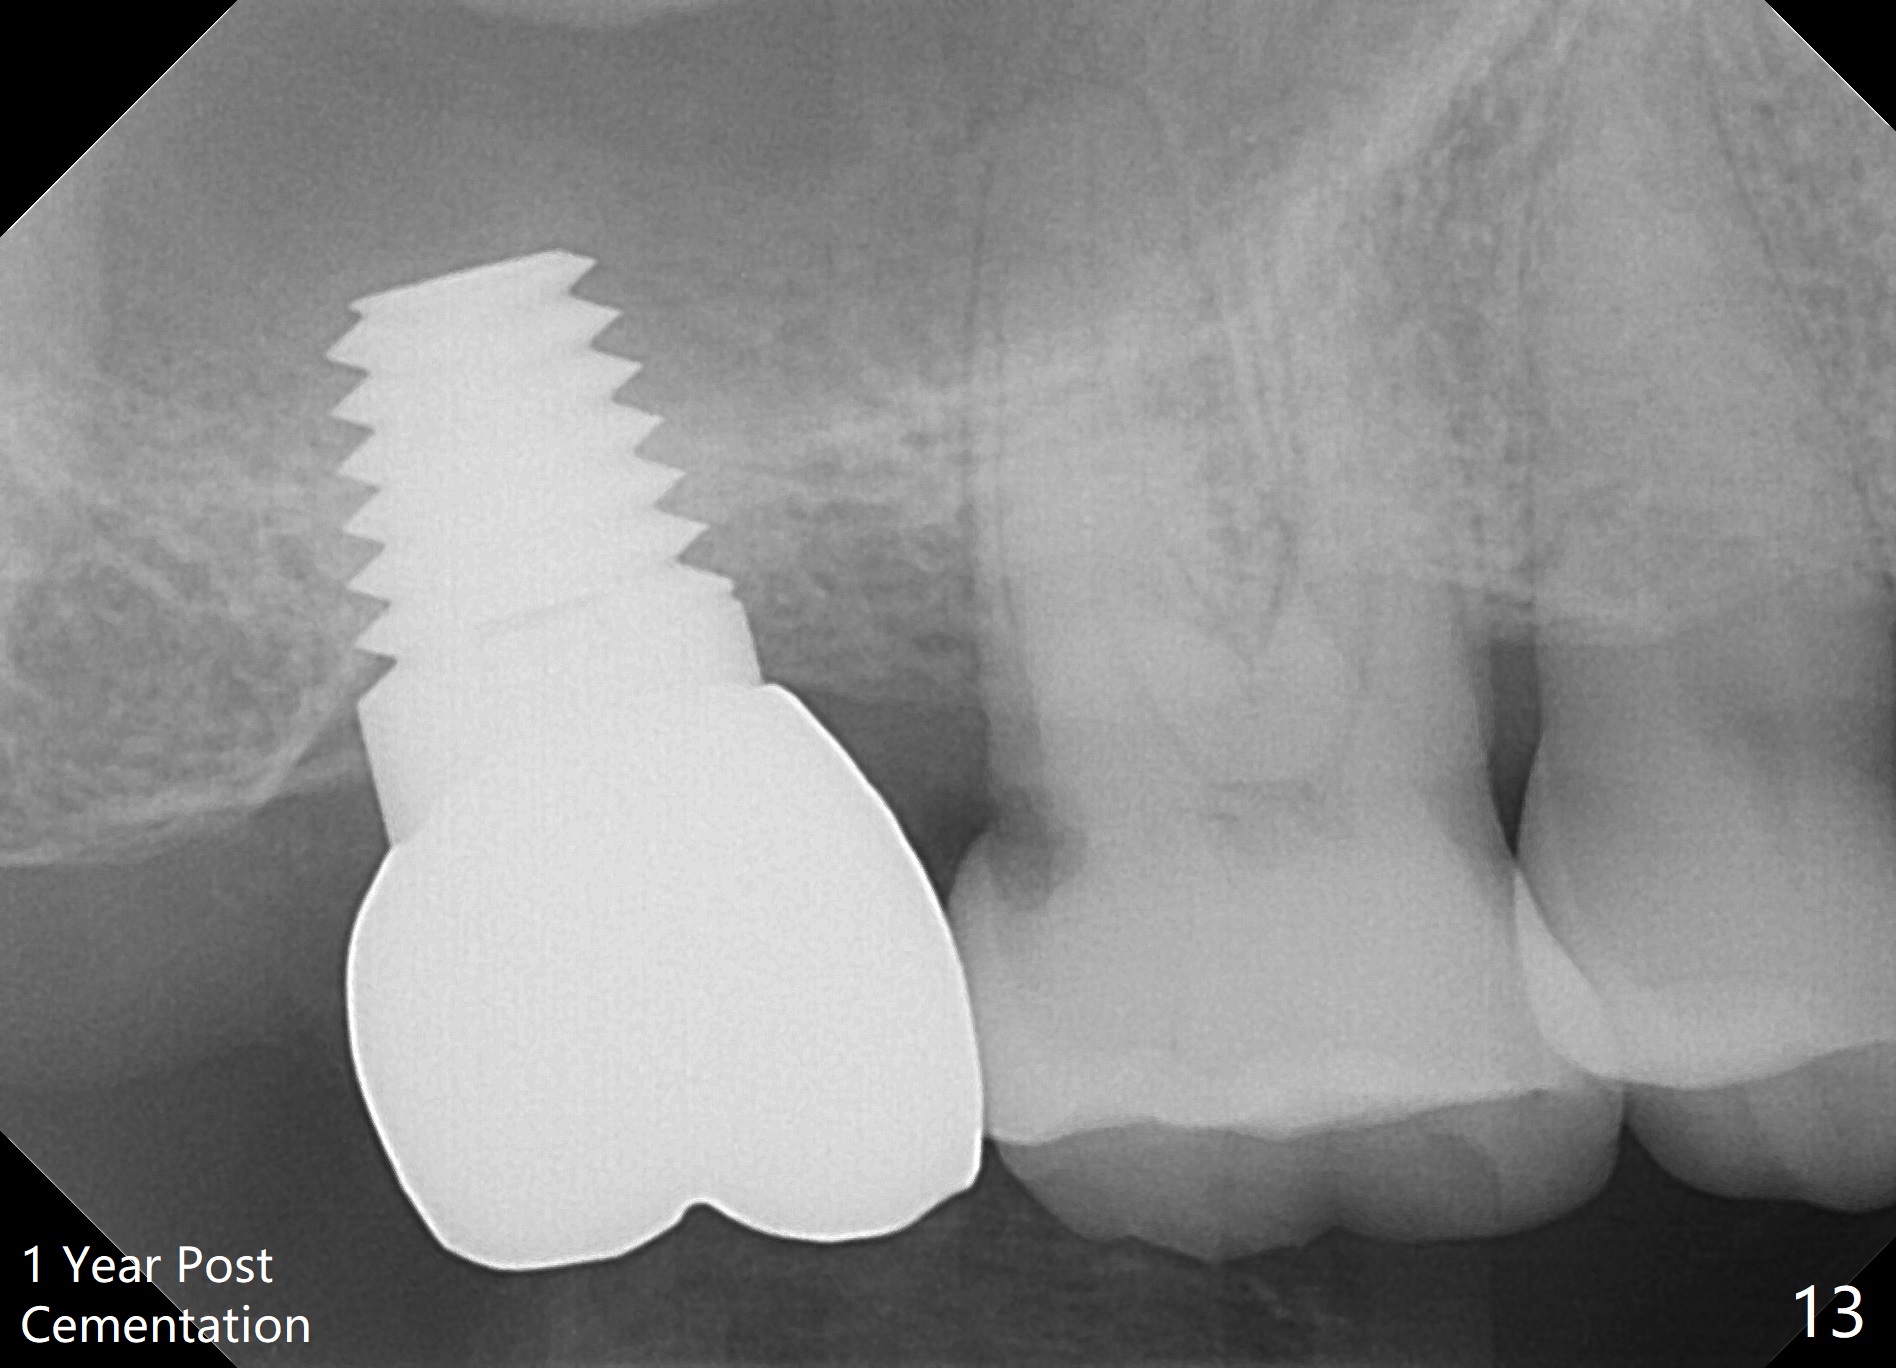

The patient returns for final restoration 22 months postop (Fig.12). Implant threads are embedded in the bone. Panoramic X-ray is taken after removal of perforated provisional and abutment. The implant remains asymptomatic 1 year post cementation (Fig.13) in spite of the fact that there appears to be no palatal plate (Fig.14 (1.5 years post cementation)). It is probably related to the thick palatal (P) gingiva. Periimplantitis develops 3 years post cementation and immediately post #15 implant 2nd removal. The implant is found to be palatal when #3 DO composite is placed (Fig.15). Oral hygiene appears to be difficult to maintain in spite of use of water pik. His diabetes is under control with Insulin.